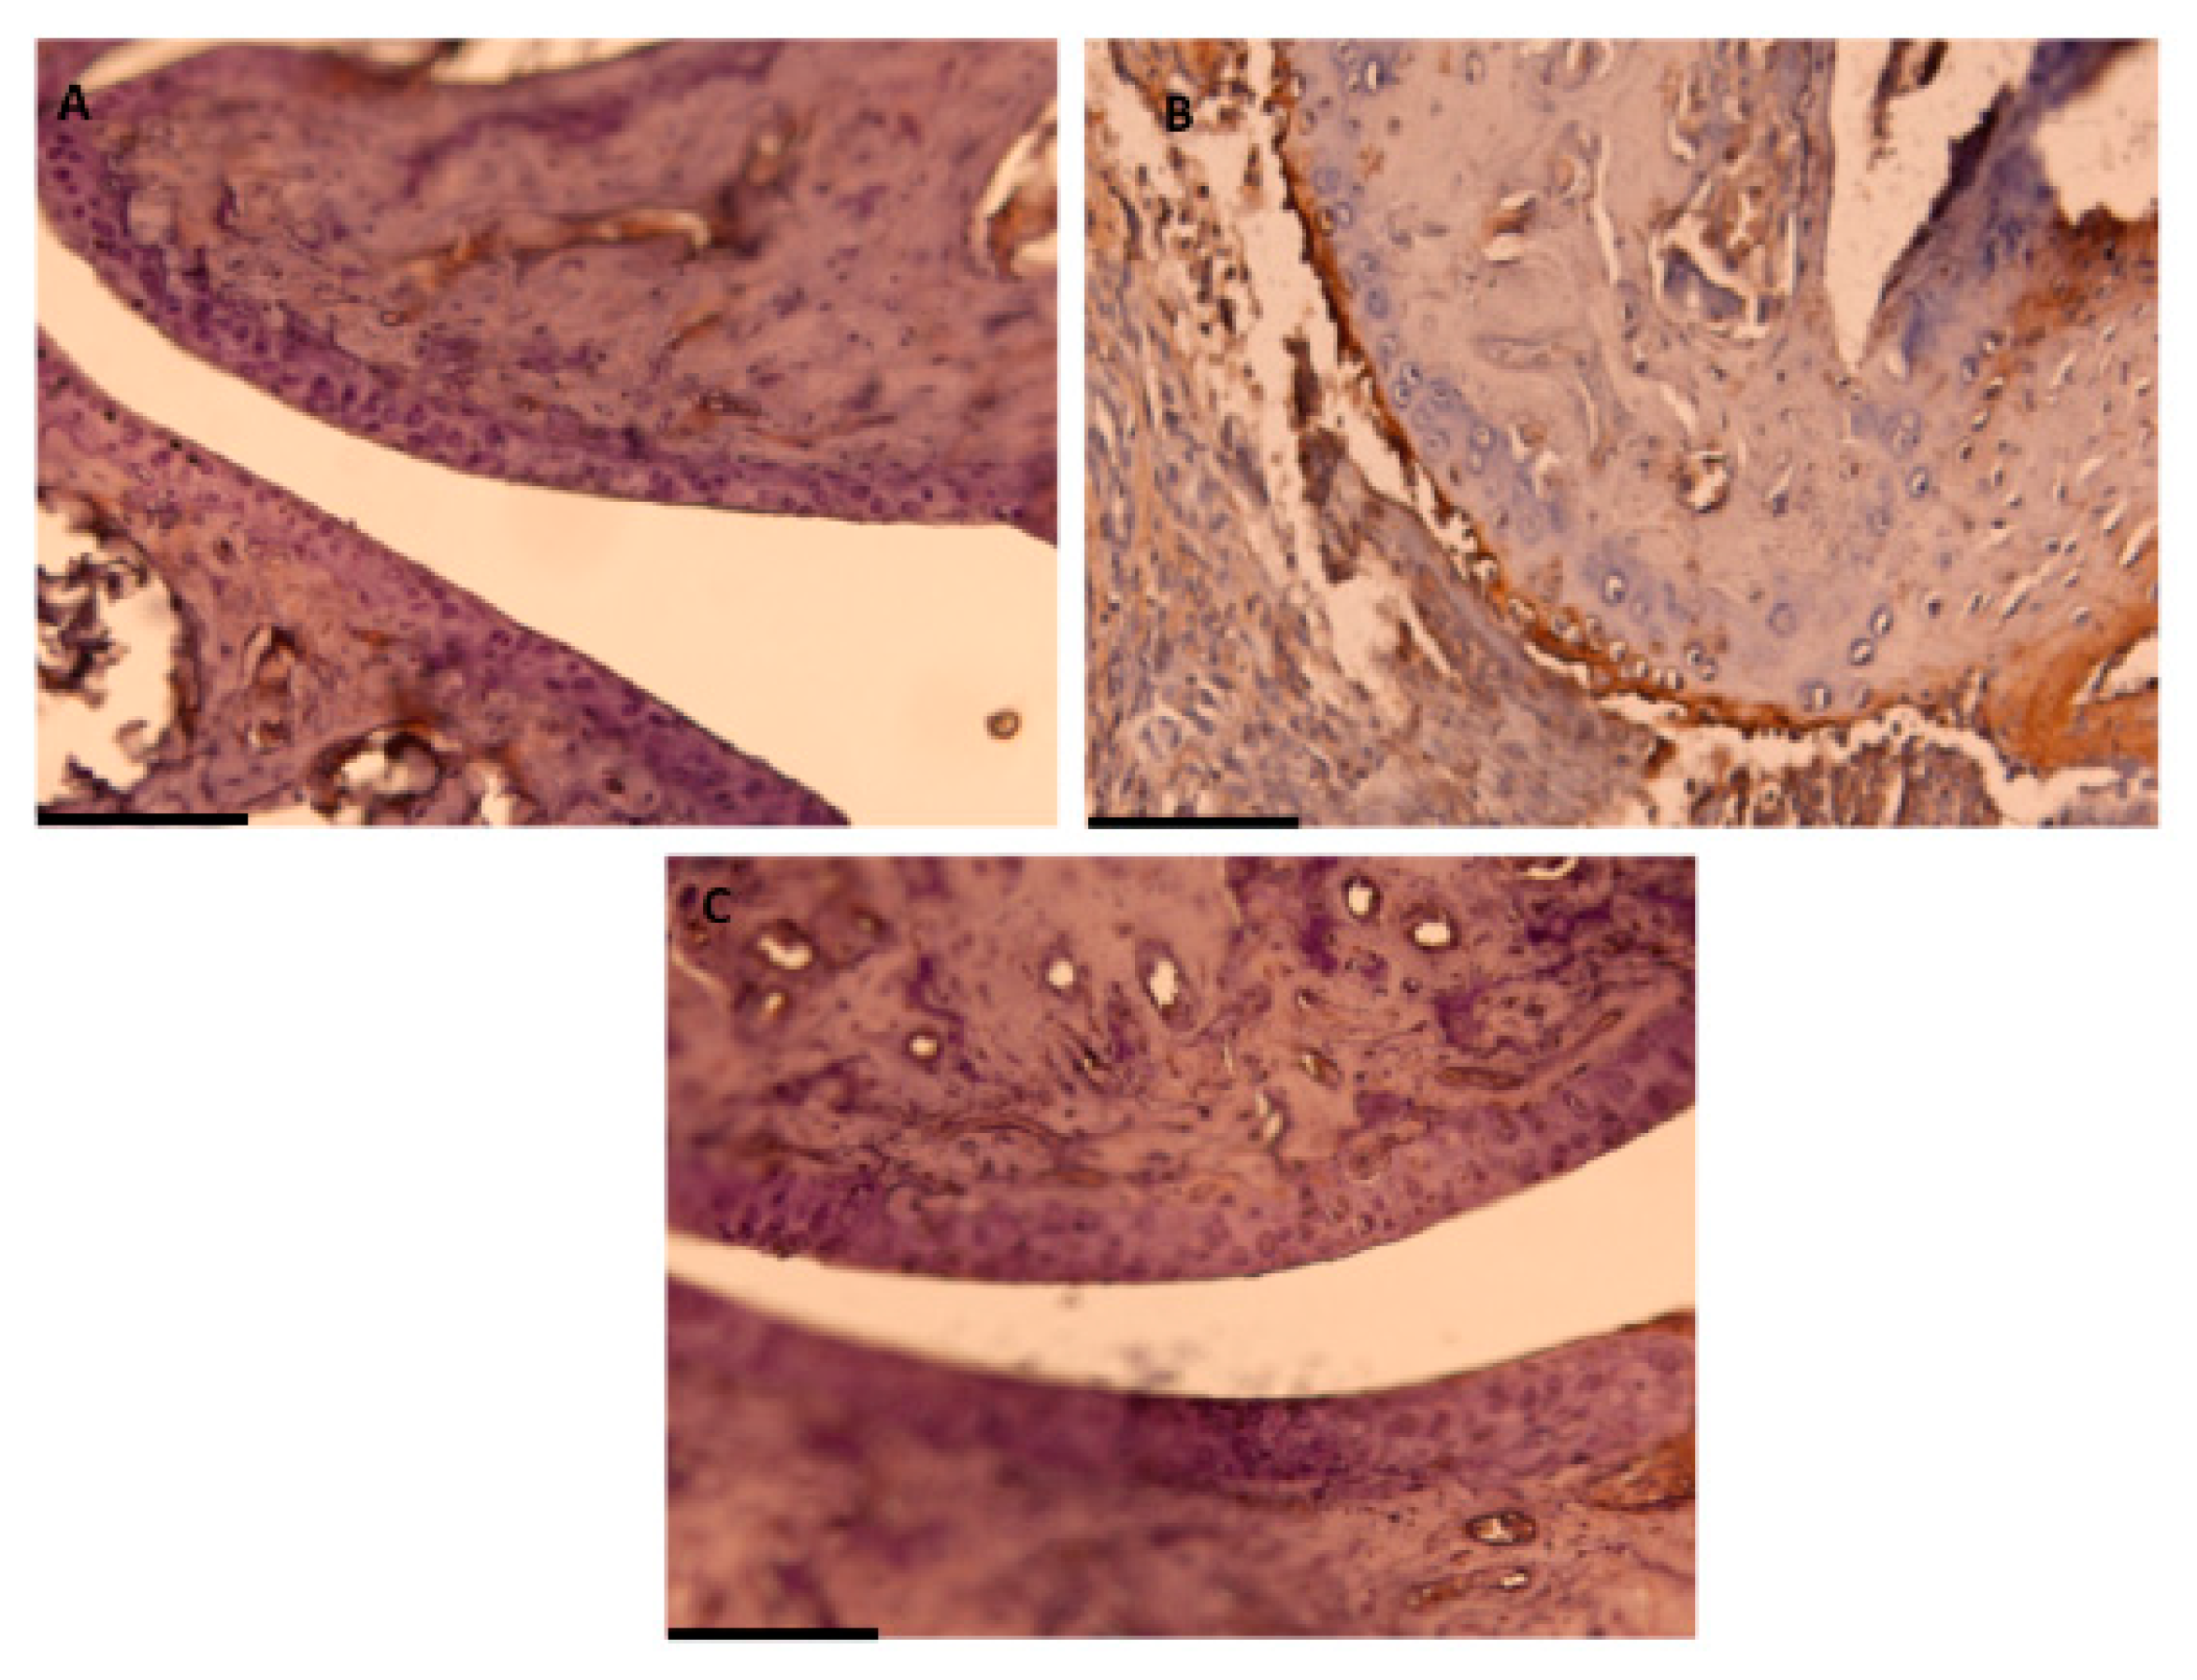

2.6. Immunohistochemical Detection of COX-2 Expression

3.3. Effects of Dietary OLE on COX-2 Protein, mPGES-1 Expression and PGE2 Production

3.4. OLE Experimental Diet Attenuated iNOS Overexpression